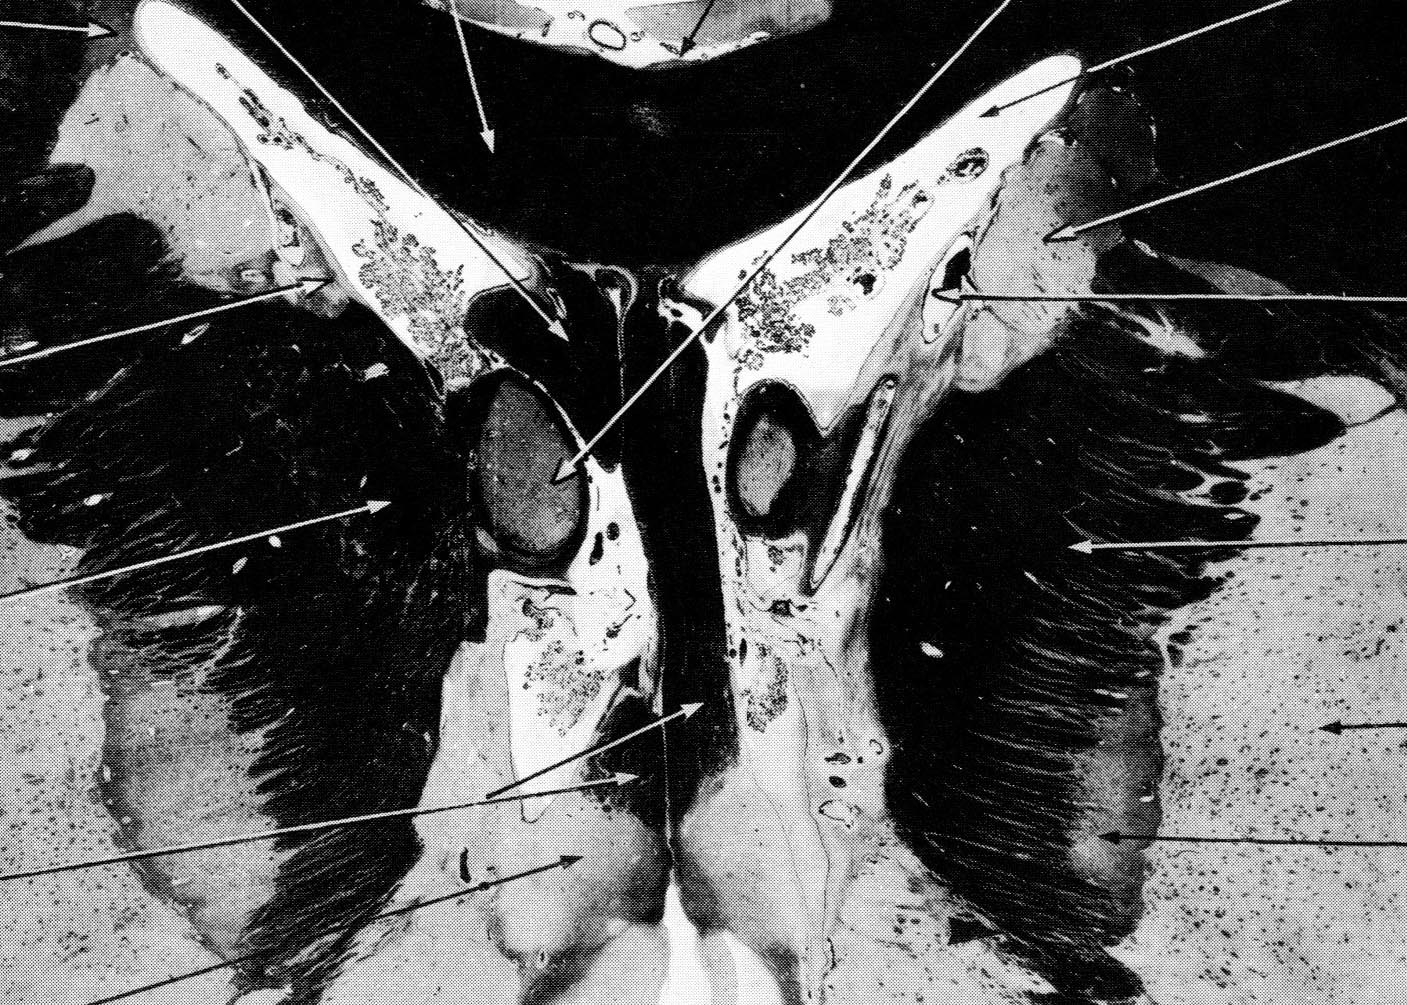

Bild: D.H. Ford, J.P. Schadé: Atlas of the Human Brain, Amsterdam, London, New York, 1966, S.112. Ein Fund in VALIE EXPORTs Bibliothek.